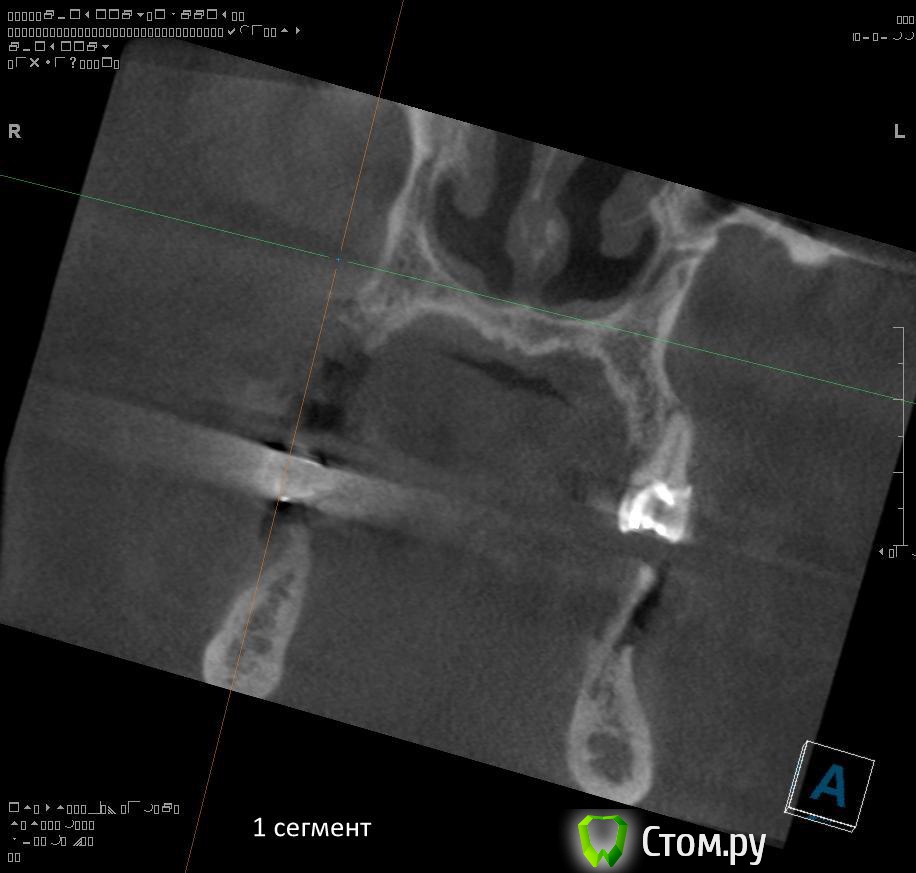

Провели обследование. Ортопед планирует оставить вверху 6 фронтальных зубов (возможно резцы пойдут на удаление), внизу только клыки. Далее последует удаление несостоятельных зубов + иммедиат протезы, продолжение реабилитации.

1. правильно ли я понимаю, что через 1,5 - 2 месяца после удаления 1.4 можно провести аугментацию (синус-лифтинг, латеральное окно, в первом сегменте, возможно с одномоментной установкой имплантатов)?

2. нужна ли в 1 сегменте дополнительная аугментация (по вертикали)?

3. в какие позиции должны быть поставлены имплантаты в 1 сегменте сбоку (1.7, 1.5)?

1. Не правильно понимаете. Покажите ЛОРу на предмет хронического гайморита и инородных тел в пазухе.

2. Не нужна. Наростить много не получится.